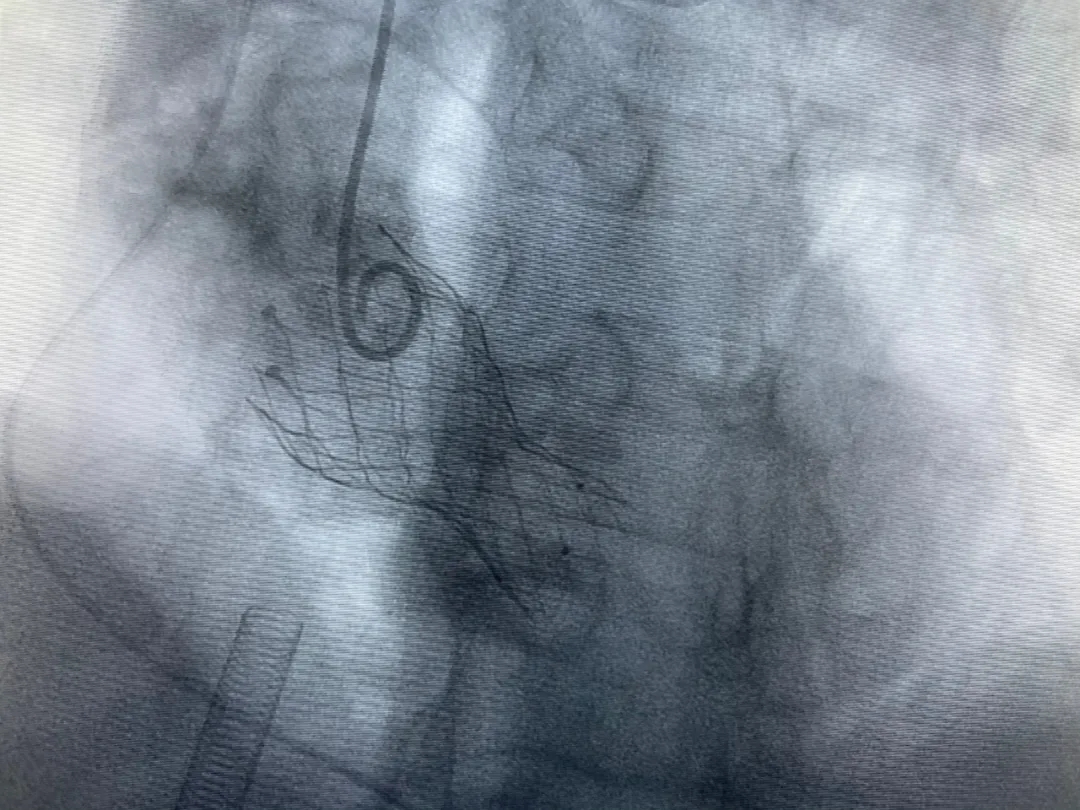

結(jié)合老人病情特點(diǎn):年齡高、室壁厚、左室腔小、瓣膜鈣化嚴(yán)重,術(shù)中球囊擴(kuò)張和瓣膜釋放過程有循環(huán)崩潰可能;為降低此種風(fēng)險(xiǎn)、最大程度提高手術(shù)成功率,張金洲副院長(zhǎng)在術(shù)前組織了由楊金保博士帶領(lǐng)的TAVR團(tuán)隊(duì)多次反復(fù)溝通、討論,制定了各種應(yīng)急處理方案。最終經(jīng)過TAVR團(tuán)隊(duì)的默契配合,手術(shù)歷時(shí)2小時(shí),用20#球囊預(yù)擴(kuò)張后順利植入23#主動(dòng)脈瓣生物瓣膜,再次后擴(kuò)后主動(dòng)脈根部造影顯示:人工主動(dòng)脈瓣生物瓣位置良好,瓣葉開閉正常;冠脈顯影良好。經(jīng)食道超聲顯示:主動(dòng)脈瓣葉活動(dòng)度良好,主動(dòng)脈跨瓣壓差約35mmHg,未見瓣周漏及明顯返流。出手術(shù)室前老人便已蘇醒,自訴憋悶癥狀完全消失。